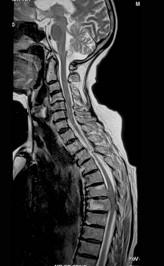

问题 女,72岁,双下肢轻度截瘫3个月余,请结合影像学检查,选出最可能的诊断 ( )

选项 A、脊柱转移瘤 B、强直性脊柱炎 C、脊椎结核 D、化脓性脊柱炎 E、椎体压缩骨折

答案 C